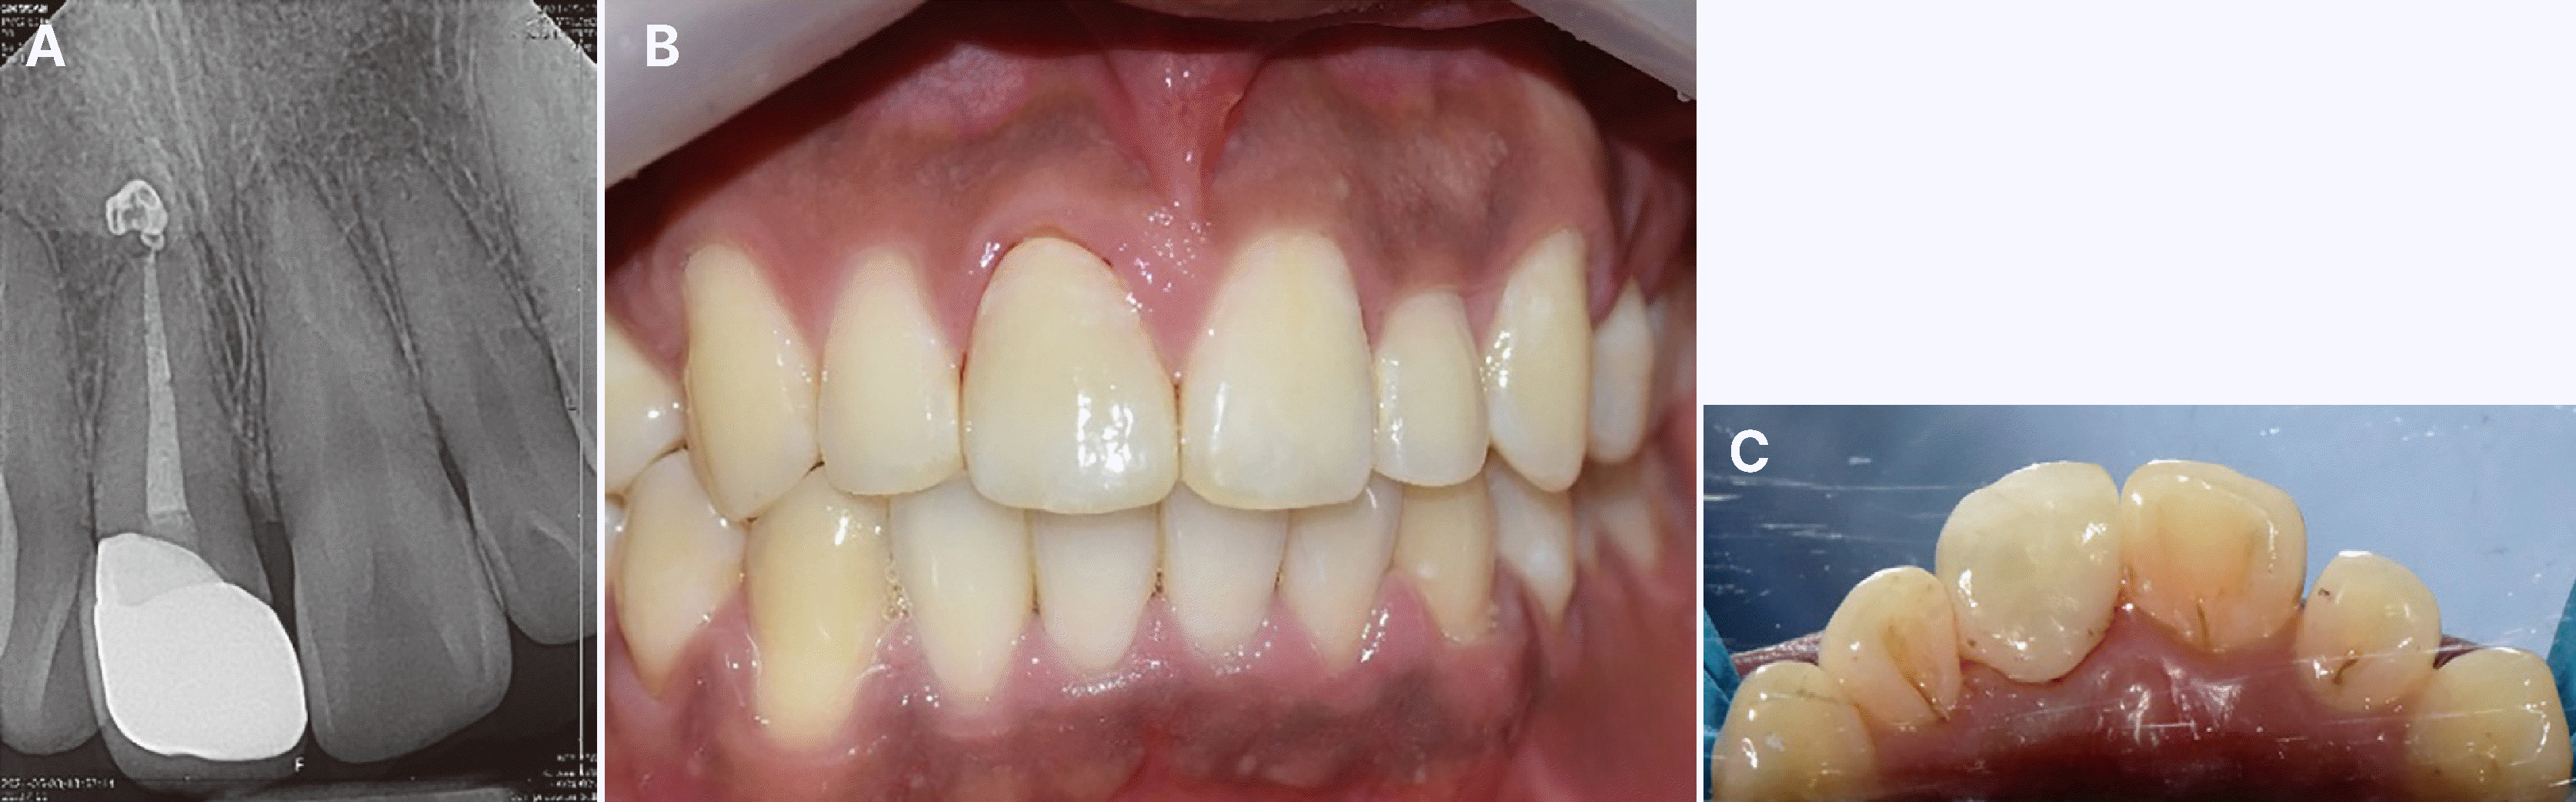

2달 경과관찰 후 임상 검사 시행 결과, 초기보다 동요도가 감소하여 생리적 범위였고, 타진 및 촉진에 불편감이 없었으며 정상적인 치주낭 깊이를 확인하였다. 방사선 사진 상 치근단 밖으로 정출된 실러가 흡수되지는 않았지만 치근 표면에 진행이 의심되는 흡수는 관찰되지 않았으며 환자의 통증이나 불편감은 없었다(Fig. 4). 최종 인상을 채득하고 도재-지르코니아 전장관으로 최종 수복물을 제작하여 레진 시멘트를 이용해 합착하였다. 6개월 및 1년 후 경과관찰 시행결과 치근단 밖으로 정출 된 실러가 흡수되지는 않았지만 치근 주변으로 골 조직이 형성되었으며 치조백선이 단절된 부분 없이 형성된 것을 확인하였다(Fig. 5, 6). 진행 중인 치근흡수나 치근 유착 또한 관찰되지 않았다. 환자의 불편감은 없었으며 동요도, 타진 반응, 치주낭 검사에 모두 음성 및 정상 범주의 결과를 관찰할 수 있었다. 다만 수복한 치아의 근심측에서 유리치은이 약간 증가한 경향이 있었는데 발치 후에 변연골이 일부 소실된 것과 치아를 정출하면서 근원심 폭이 감소하여 발생한 공간으로 치은이 증식한 것이 원인으로 분석되었다.

Fig. 4

2 months follow up. (A) Radiograph of maxillary right central incisor, (B) Temporary crown state.